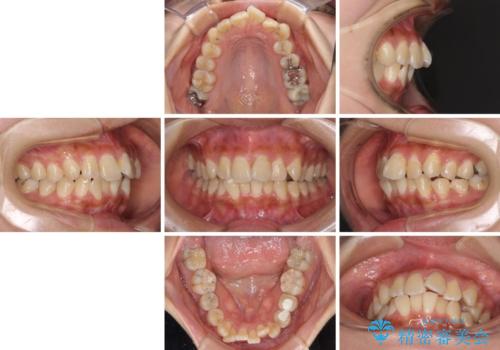

デコボコで磨きにくい前歯をスッキリと インビザライン矯正

- 虫歯が多く、磨きにくい歯並びを改善したいとのことで来院された患者様です。

歯列は叢生が認められる程度でしたが、やや前突感があったので、少しでも口が閉じやすくなるように仕上げる方針としました。

神経を取り除かれている歯3本以外にも虫歯が認められたため、事前に処置を行い、インビザラインにて矯正治療を行うこととしました。

神経が取り除かれている歯は、クラウンによる補綴治療が必要であるため、矯正治療後にオールセラミッククラウンにて補綴治療を行うこととしました。

歯磨きしやすくなるとともに、飛び出していた前歯も引っ込めて整えることができました。